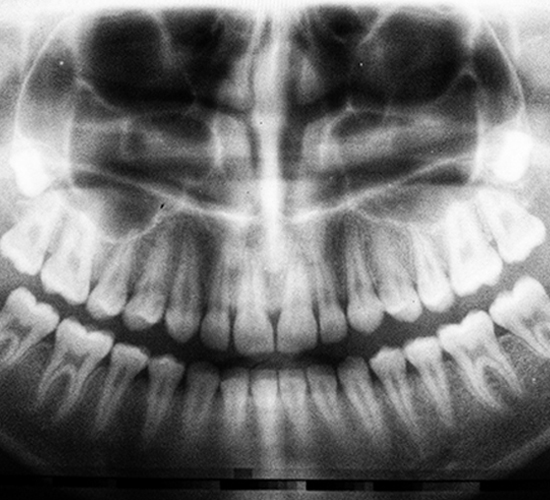

Dental professionals today are increasingly using digital dental radiographs (digital X-rays) to better detect, diagnose, treat, and monitor oral conditions and diseases.